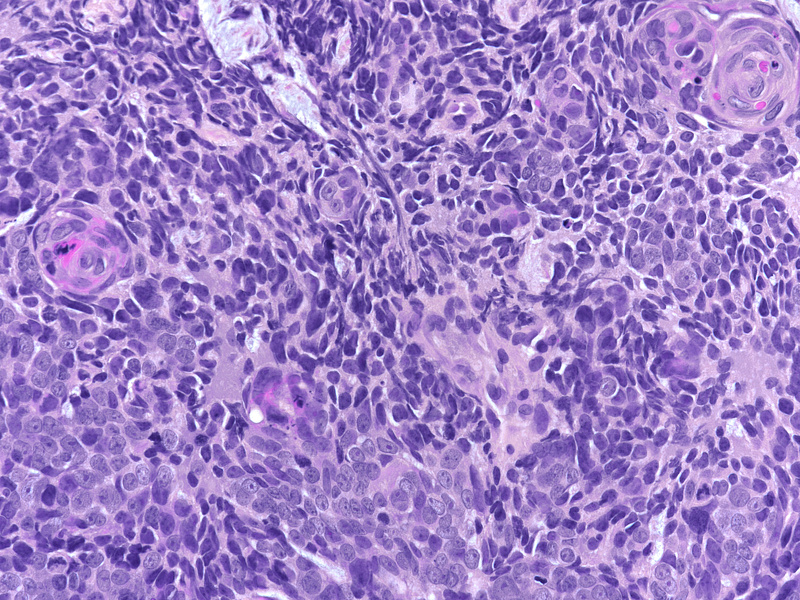

On low power the lesion is composed of sheets of monomorphic, overlapping small to medium sized malignant cells with irregular nuclear contours and finely dispersed chromatin without well-formed nucleoli (Panels A-B). Within these sheets of cells are demarcated areas of squamous differentiation, with formation of clearly visible squamous eddies and focal high-grade cytology (Panels C-D).

The immunohistochemical staining shows that the sheets of monomorphic cells show immunoreactivity for CD56 and synaptophysin (Panel E) and have a high proliferation index on ki67 staining (Panel F) proving neuroendocrine differentiation (neuroendocrine carcinoma, NEC). Of note, both areas of neuroendocrine and squamous differentiation show diffuse nuclear p40 immunoreactivity (Panel G) while cytokeratin positivity with CK5/6 is restricted to areas of squamous differentiation visible already on H&E, indicating more mature cells (Panel H). This reciprocal immunoprofile, taken together with the biphasic morphological pattern described above, is that of a mixed neuroendocrine-non-neuroendocrine neoplasm (miNEN).

In these lesions, the neuroendocrine component often has a high proliferative index (ki67 >55%), with an associated higher risk of metastasis (3) and shows immunoreactivity for the neuroendocrine markers such as CD56, synaptophysin and chromogranin A, as can be seen in our case. The non-neuroendocrine component, in our case, shows positivity for p40 and cytokeratin, the immunoprofile of a squamous cell carcinoma. Prognosis is largely dependent upon grade and stage, with grading using the same system for other gastroenteropancreatic neuroendocrine neoplasms.